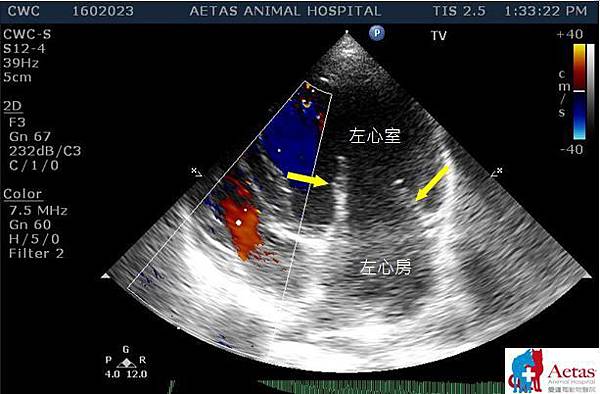

此圖為有慢性瓣膜性疾病的犬隻的心臟超音波示意圖,圖中白色字體標示出左心房跟左心室的位置。黃色箭頭則標示出左心的兩片瓣膜,可以看到因為老化的原因造成的瓣膜增厚及扭曲,進而使得左心室跟左心房的腔室擴大。